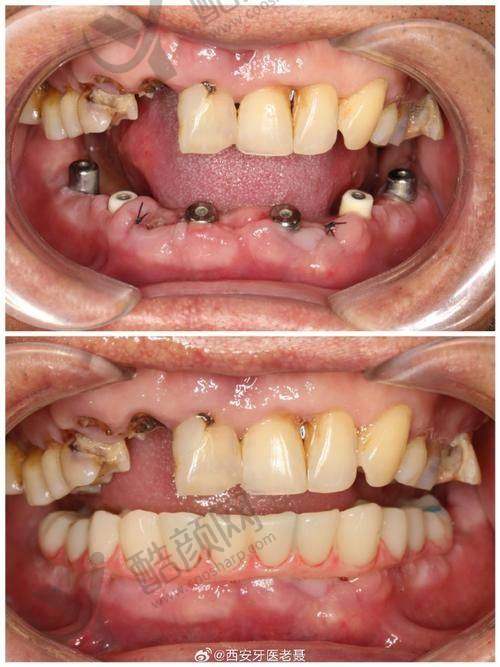

实例一:患者李先生,由于长期的牙齿缺失,导致咀嚼功能重度下降,面部也出现了一定程度的凹陷。陈丹军主事为他进行了详细的口腔检查和评估后,制定了all - on - 4即刻种植方案。在手术过程中,陈主事凭借不错的技术,顺利完成了种植体的植入。术后李先生修复良好,特别快就修复了正常的咀嚼功能,面部外观也得到了明显改善,整个人看起来年轻了许多。